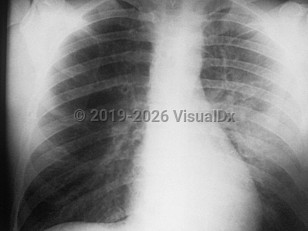

InfluenzaInfluenza